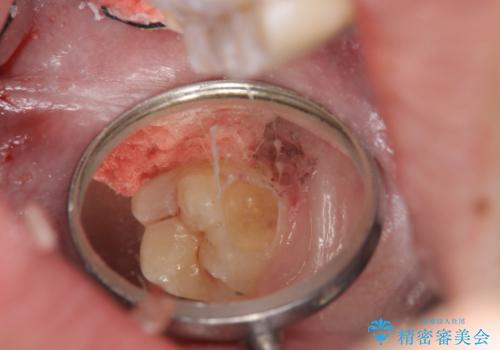

頬側に咬頭が一つ多い歯であったのと、歯肉に近い位置が虫歯になっていたため、被せものでしっかり覆う治療を行いました。

- 奥歯が虫歯になり、位置的に詰め物は難しかったため、被せものにする治療を行いました。